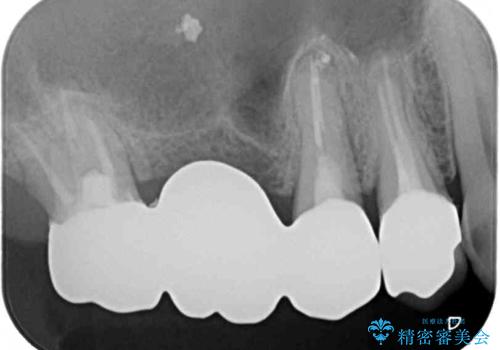

- 咬んだときに奥歯に痛みを感じるとのことで来院された患者様です。

診査の結果、左側は奥歯2本、右側は1本の抜歯が必要であることが分かりました。

左側は大臼歯2本と小臼歯1本が欠損しているため、インプラント2本を治療したブリッジ、右側は中間欠損であり、前後の歯も加療が必要であったためブリッジによる補綴治療を行うこととしました。

抜歯となった歯は全て神経が抜かれた歯であり、強大な咬合力によって破折したことが原因で抜歯となりました。